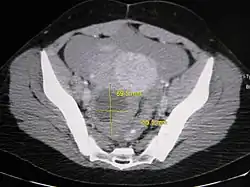

Imaging

Further work up involves imaging, such as a pelvic ultrasound or CT scan.[7] Theca lutein cysts with diameters over 6 cm in size can be seen through these imaging modalities.[18] Benign ovarian cysts and complex cysts that are potentially malignant are distinguishable via ultrasounds.[19] Labs are also collected to evaluate leukocytes and tumor markers, such as beta-hCG and cancer antigen 125 (CA125).[20]

During pregnancy, ultrasonography is the first-line method for evaluating ovarian cysts. Both transabdominal and transvaginal route of ultrasonography are used with either two-dimensional or three-dimensional modalities.[3] Two-dimensional is more common, but three-dimensional can offer more results.[3] Doppler ultrasonography can also be used and is helpful at analyzing the characteristics of the cyst.[3] It can identify the presence of color flow within a septum as well as the presence of a solid component of the mass.[3] Ultrasonography is an effective tool for observing the progression or regression of the cyst.[3] Magnetic resonance imaging (MRI) is the second-line method used when ultrasonography cannot detect the cyst.[3] Cysts that are too large to be accurately analyzed by ultrasonography are typically when MRI would be used.[3] The advantages of MRI are its larger field of view and multiplanar capabilities.[21] In addition, pathologies such as infarctions and placental invasive disorders can be seen more clearly.[3] MRI is especially beneficial in gestational age and obese people.[3] MRI is also beneficial at preventing the exposure of ionizing radiation to the fetus during pregnancy.[22] Both ultrasonography and MRI show enlarged ovaries with multiple theca lutein cysts.[3]